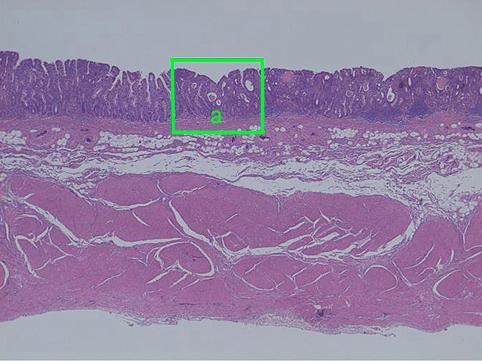

clasificación del pacienteTumor Epitelial Maligno/Adenocarcinoma

método de exámenMicro

clasificación ectoscópica de tumoresTipo 0(tipo superficial)/Tipo IIb(IIb+IIa)

grado de penetraciónm